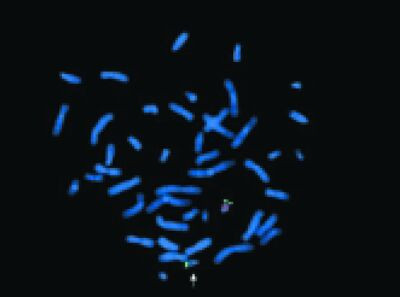

Genetische diagnostiek en erfelijkheidsadvisering nu en in de nabije toekomst

De publicatie van een eerste voorlopige genenkaart van de mens begin 2001 was een zeer belangrijke wetenschappelijke mijlpaal en heeft ook veel aandacht gekregen in de media. Voor de dagelijkse praktijk binnen de klinische genetica, die vooral gericht is op erfelijkheidsadvisering, was het…